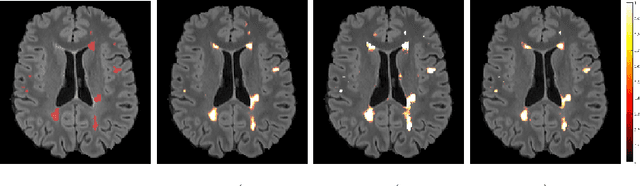

Abstract:The current multiple sclerosis (MS) diagnostic criteria lack specificity, and this may lead to misdiagnosis, which remains an issue in present-day clinical practice. In addition, conventional biomarkers only moderately correlate with MS disease progression. Recently, advanced MS lesional imaging biomarkers such as cortical lesions (CL), the central vein sign (CVS), and paramagnetic rim lesions (PRL), visible in specialized magnetic resonance imaging (MRI) sequences, have shown higher specificity in differential diagnosis. Moreover, studies have shown that CL and PRL are potential prognostic biomarkers, the former correlating with cognitive impairments and the latter with early disability progression. As machine learning-based methods have achieved extraordinary performance in the assessment of conventional imaging biomarkers, such as white matter lesion segmentation, several automated or semi-automated methods have been proposed for CL, CVS, and PRL as well. In the present review, we first introduce these advanced MS imaging biomarkers and their imaging methods. Subsequently, we describe the corresponding machine learning-based methods that were used to tackle these clinical questions, putting them into context with respect to the challenges they are still facing, including non-standardized MRI protocols, limited datasets, and moderate inter-rater variability. We conclude by presenting the current limitations that prevent their broader deployment and suggesting future research directions.

Abstract:Multiple sclerosis (MS) is an inflammatory and neurodegenerative disease characterized by diffuse and focal areas of tissue loss. Conventional MRI techniques such as T1-weighted and T2-weighted scans are generally used in the diagnosis and prognosis of the disease. Yet, these methods are limited by the lack of specificity between lesions, their perilesional area and non-lesional tissue. Alternative MRI techniques exhibit a higher level of sensitivity to focal and diffuse MS pathology than conventional MRI acquisitions. However, they still suffer from limited specificity when considered alone. In this work, we have combined tissue microstructure information derived from multicompartment diffusion MRI and T2 relaxometry models to explore the voxel-based prediction power of a machine learning model in a cohort of MS patients and healthy controls. Our results show that the combination of multi-modal features, together with a boosting enhanced decision-tree based classifier, which combines a set of weak classifiers to form a strong classifier via a voting mechanism, is able to utilise the complementary information for the classification of abnormal tissue.

Abstract:In this work, we present a comparison of a shallow and a deep learning architecture for the automated segmentation of white matter lesions in MR images of multiple sclerosis patients. In particular, we train and test both methods on early stage disease patients, to verify their performance in challenging conditions, more similar to a clinical setting than what is typically provided in multiple sclerosis segmentation challenges. Furthermore, we evaluate a prototype naive combination of the two methods, which refines the final segmentation. All methods were trained on 32 patients, and the evaluation was performed on a pure test set of 73 cases. Results show low lesion-wise false positives (30%) for the deep learning architecture, whereas the shallow architecture yields the best Dice coefficient (63%) and volume difference (19%). Combining both shallow and deep architectures further improves the lesion-wise metrics (69% and 26% lesion-wise true and false positive rate, respectively).